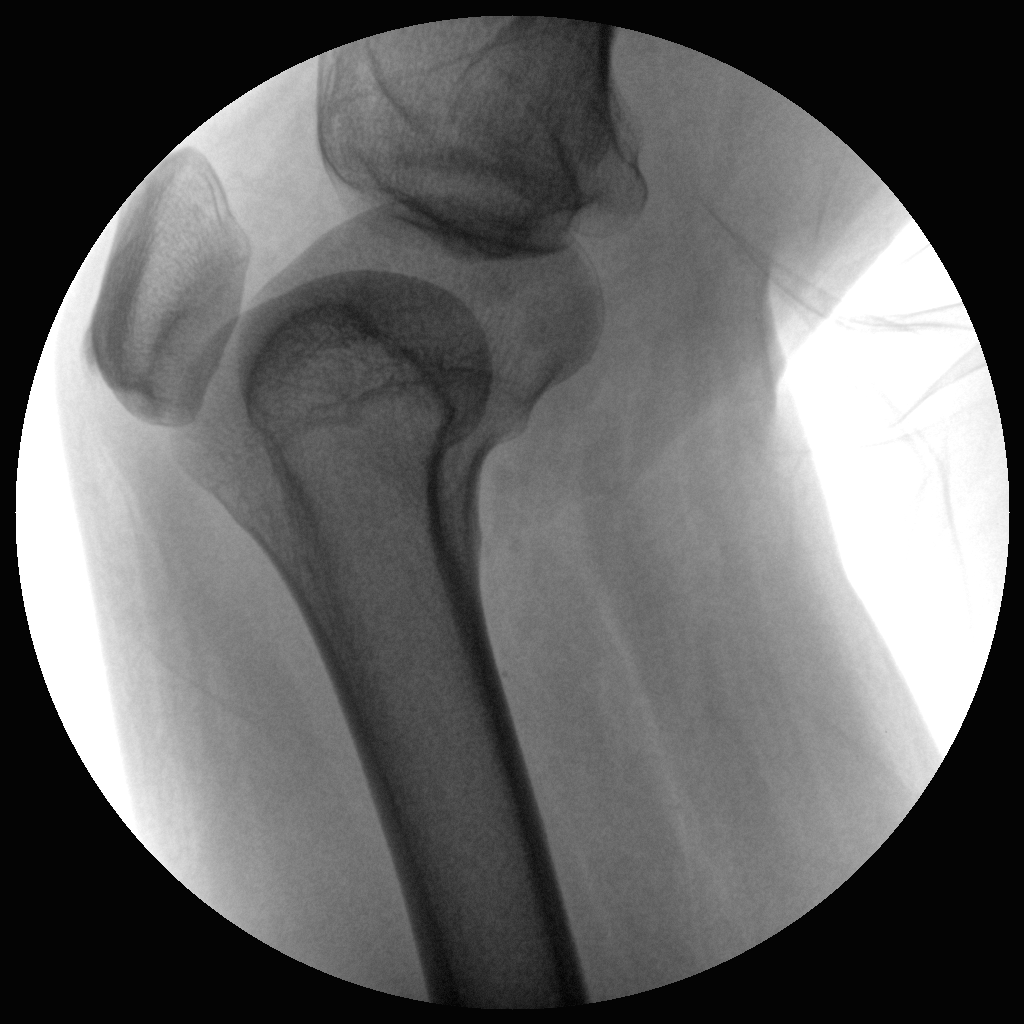

●經(jīng)典影像工作站,可隔室操作避免輻射

●全數(shù)字化百萬(wàn)像素影像系統(tǒng),圖像清晰

●靈活的C臂機(jī)架設(shè)計(jì),滿足臨床大范圍運(yùn)動(dòng)

●臨床功能豐富,具備脈沖控制、數(shù)字?jǐn)z影、自動(dòng)透視等